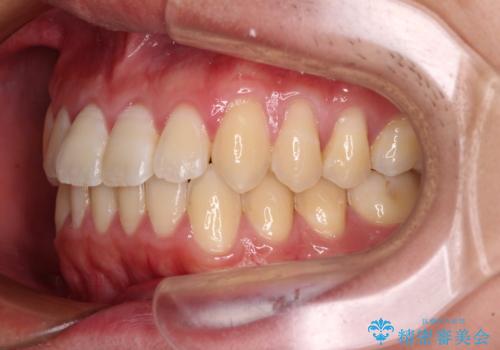

- 上下前歯のデコボコを気にして来院された患者様です。

叢生は軽微であり、費用を抑えて期間もあまりかけずに治療をしたいとのことで、インビザライン・ライトを用いて矯正治療を行うこととしました。

途中通院できなくなり、マウスピースの装着もしっかりとできなかったため、治療期間が長くかかってしまいました。